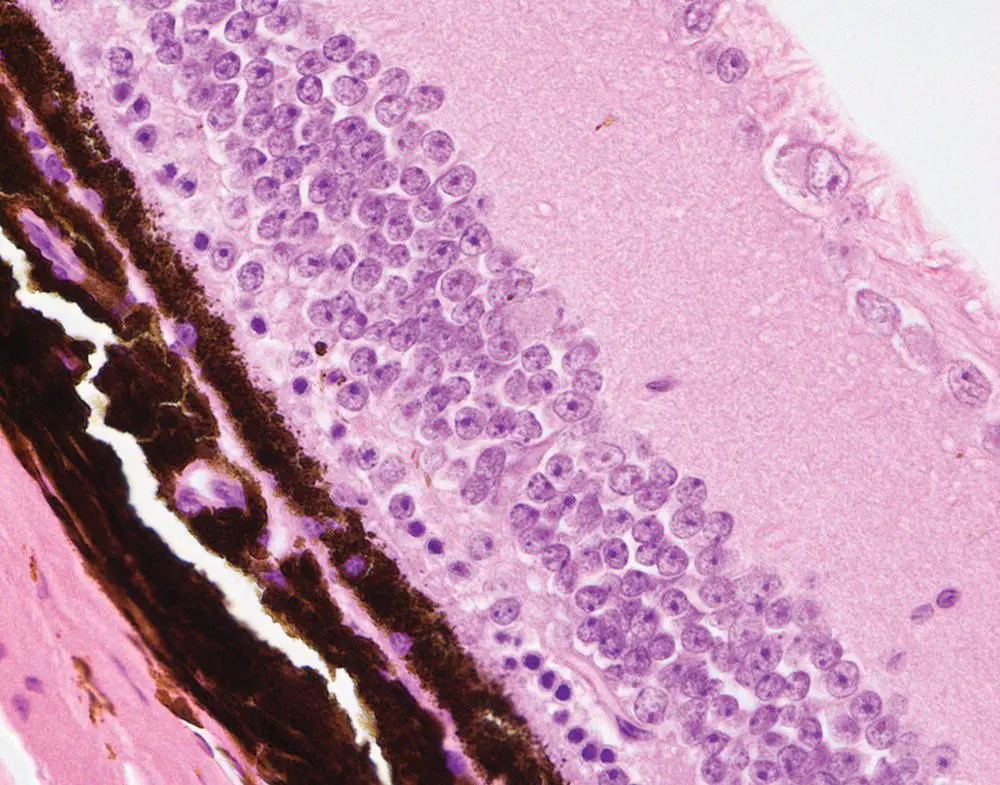

Histology is a very sensitive and specific method for detecting retinopathies. In normal mouse eyes, subretinal macrophages are absent or very rare, the inner and outer segments of the photoreceptors appear in organized columns and are of approximately equal length, and the outer nuclear layer is thicker than the inner nuclear layer. Almost all disruptions affecting the development or function of outer segments will lead to degeneration of photoreceptors, which can be detected histologically even at early stages by the appearance or any combination of the following changes: increased numbers of subretinal macrophages ( Figure 6.6), disrupted/thin outer segments, or reduced thickness of the outer nuclear layer (consisting of photoreceptor nuclei; Figure 6.7).

Figure 6.6 Eye. Macrophages within the outer segment of photoreceptor are present at the earlier stages of retinal degeneration.

Figure 6.7 Eye. Advanced retinal degeneration there is characterized by a marked reduction in the thickness of the outer nuclear layer photoreceptors.